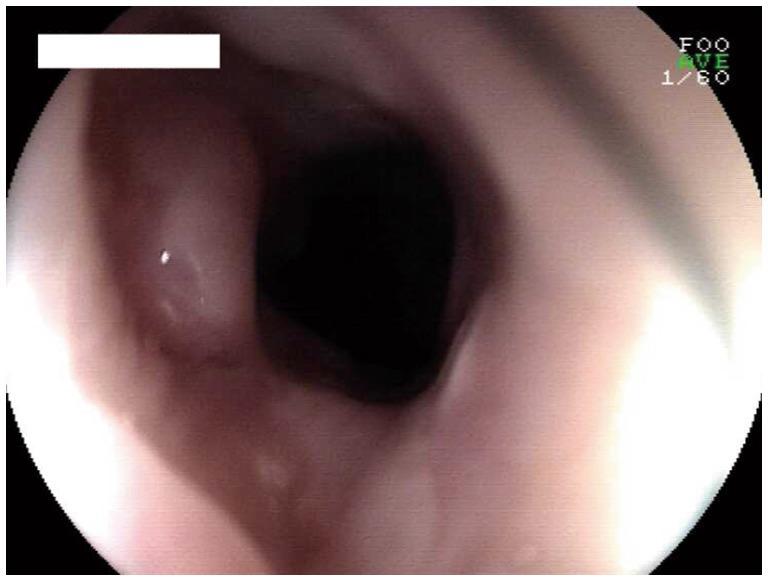

病例报告:内镜胆道附件在一名完全性食管狭窄患者中的成功应用。

Case Report: Successful application of endoscopic biliary accessories in a patient with complete esophageal stricture.

The endoscopic treatment of complete esophageal stricture presents a huge challenge. In instances where the esophageal lumen is nearly obliterated, preventing the passage of a dilating guide wire, conventional endoscopic bougie dilation is often difficult to perform. We report a case of patients with nearly complete esophageal stricture due to esophageal cancer surgery, leading to severe dysphagia and weight loss. Our strategy began with the achievement of anterograde esophageal access, facilitated by a biliary intubation method and aided by a 0.35-inch guidewire. Subsequently, we sequentially applied biliary dilators and balloon dilators, progressing along the guidewire to incrementally dilate the esophageal lumen up to the site of complete stenosis. The stenosis was successfully penetrated and dilated, and eventually the patient's dysphagia was completely relieved. This case underscores the efficacy of the novel endoscopic treatment for biliary appendices in patients with refractory esophageal anastomotic stricture, offering a new therapeutic approach for clinical management.

摘要

完全性食管狭窄的内镜治疗是一项巨大挑战。在食管腔几乎闭塞、无法通过扩张导丝的情况下,传统的内镜探条扩张术往往难以实施。我们报告一例因食管癌手术导致几乎完全性食管狭窄的患者,患者出现严重吞咽困难和体重减轻。我们的策略首先是通过胆道插管法实现顺行性食管通路,并借助一根0.35英寸的导丝辅助。随后,我们沿导丝依次应用胆道扩张器和球囊扩张器,逐步扩张食管腔直至完全狭窄部位。成功穿透并扩张了狭窄部位,最终患者的吞咽困难完全缓解。该病例强调了新型内镜治疗对难治性食管吻合口狭窄患者的疗效,为临床管理提供了一种新的治疗方法。